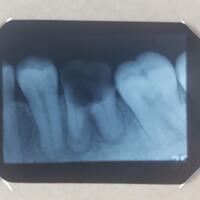

Siang Dok Mau tanya nih, 2 Minggu yang lalu gigi saya sakit. Agak ngilu gitu. Nah kemudian saya ke dokter gigi minggu depannya, menurut dokternya ada abses di gigi geraham kiri bawah M2. Dan ada Gigi yang impaksi. Setelah itu dikasih obat Albiotin dan disuruh rontgen panoramic. Sehabis obat abis sa

Dok melanjutkan pembicaraan tentang masalah rahang miring dan kawat gigi. Saya memutuskan untuk memasang kawat gigi. Sebelumnya saya melakukan foto panoramik untuk melihat gigi saya secara keseluruhan. Dari foto diketahui bahwa ada dua wisdom teeth rahang bawah (sisi kiri 1 sisi kanan 1) yang im